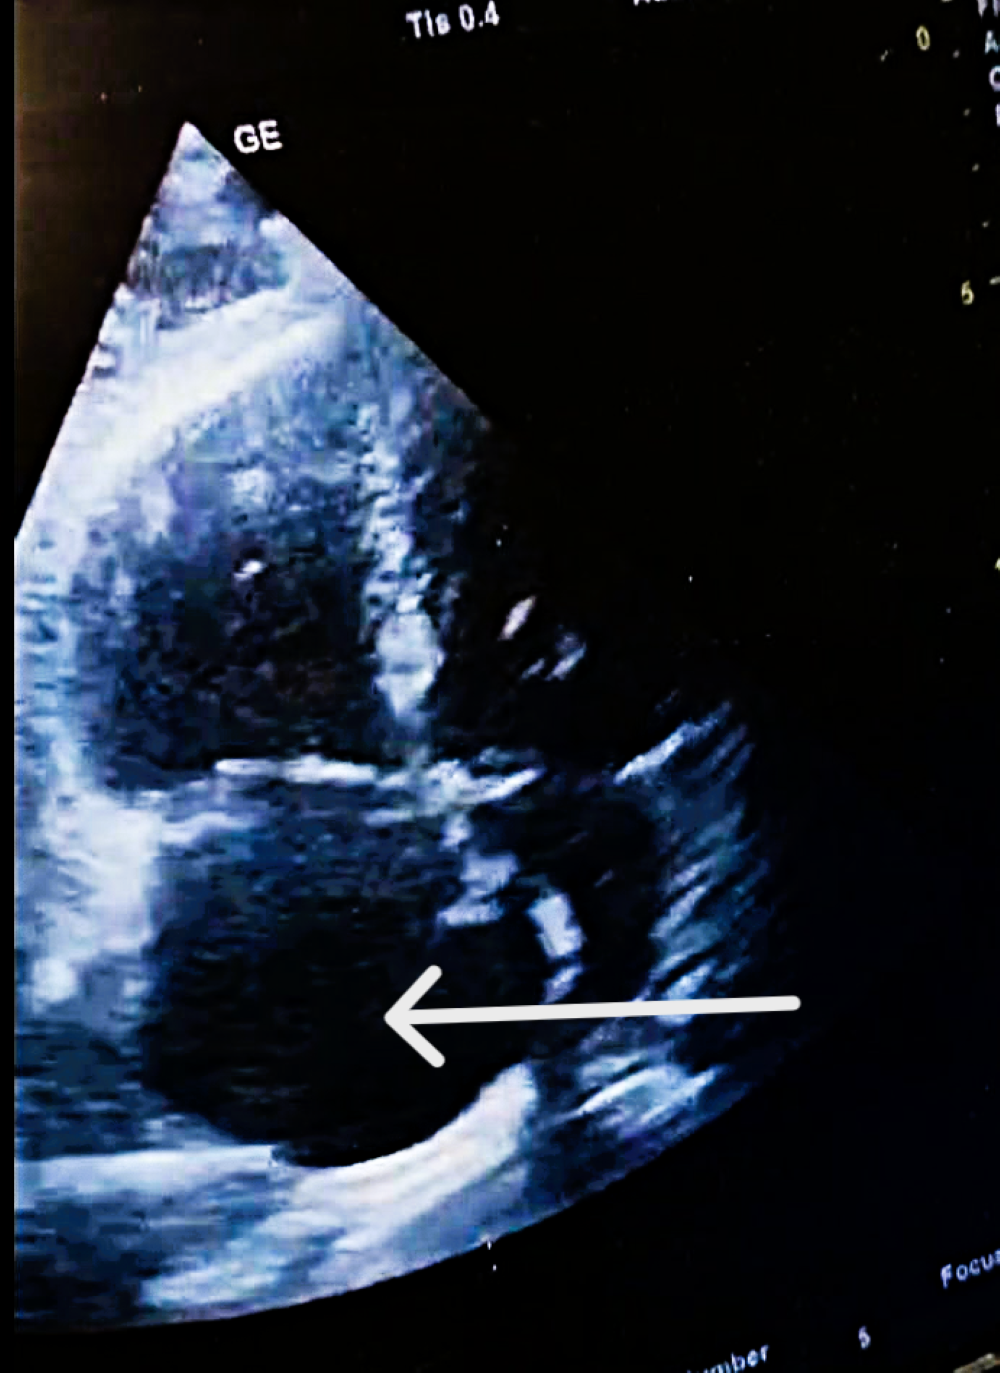

| POCUS-TTE—Parameters, Values and Risk Classification | |||

| RV/LV ratio | 1.39 | high | Intermediate-high-risk |

| TAPSE (mm) | 12 | low | Intermediate-high-risk |

| RV diameter | 46 mm (below tricuspid/pulmonary annulus) | Marked RV dilation |

| LV diameter | 33 mm | Normal size |

| RV/LV ratio | >1 | Consistent with acute RV pressure overload |

| RA size | Dilated | Elevated right-sided pressures |

| Pulmonary trunk diameter | 31 mm | Mild dilation; acute pulmonary hypertension |

| Tricuspid regurgitation, Vmax | 3.2 m/s | Increased RV pressure |

| RV—RA gradient | 40 mmHg | Significant RV overload |

| TAPSE | 12 mm | Markedly reduced RV systolic function |

| IVC | 19 mm, <50% collapse | Elevated RA pressure |

| Interventricular septum | Paradoxical motion | “D-shaped” LV; RV overload |

| Mobile RA thrombus | Large, serpentine, prolapsing through tricuspid | High embolic risk |